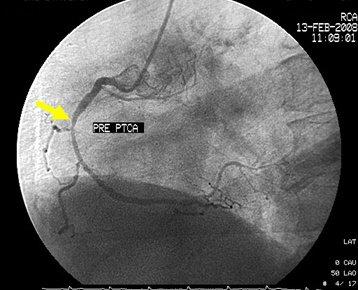

2.配合医生穿刺:一般采用Seldingers经皮穿刺法。病人取仰卧位,局麻后﹙儿童采用全身麻醉﹚在严格的无菌操作下自股静脉、上肢贵要静脉、锁骨下静脉$2右心导管术$3或股动脉、肱动脉$2左心导管术$3插入导管到达相应部位。整个检查均在X线透视下进行,并作连续的心电和压力监测。动脉穿刺成功后注入肝素3000U,随后操作每延长lh追加肝素1000U。